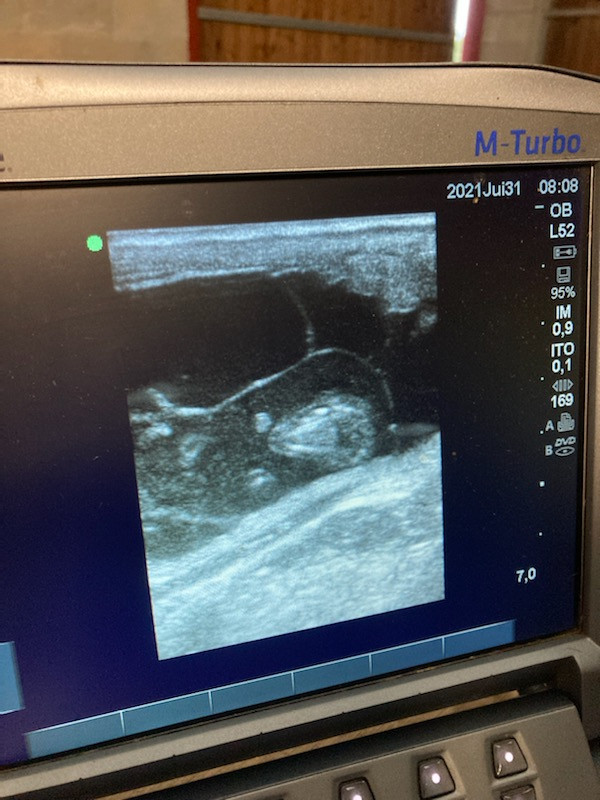

Ici, l'humeur est morose. La véto doit venir demain pour une échographie.

On se demande avec le gérant si Indeep n'aurait pas coulé en début de gestation.

C'est difficile à déterminer car c'est sa première gestation mais elle est à 8 mois et sa morphologie n'a pas bougé d'un iota (pas de ventre, je ne sens pas non plus le poulain).